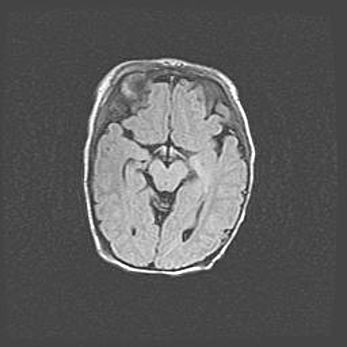

Открытая гидроцефалия.

Возраст: 9 месяцев 12 дней

Вес: 6800 г

Пол: мужской

Окружность головы: 41,5 см

Срок гестации: 28 недель

Гидроцефалия головного мозга у новорожденных имеет характерный признак: опережающий рост окружности головы приводит к визуально хорошо определяемой гидроцефальной форме сильно увеличенного в объёме черепа. Детские неврологи определяют следующие симптомы гидроцефалии у грудничков: выбухающий напряжённый родничок, частое запрокидывание головы, смещение глазных яблок к низу.